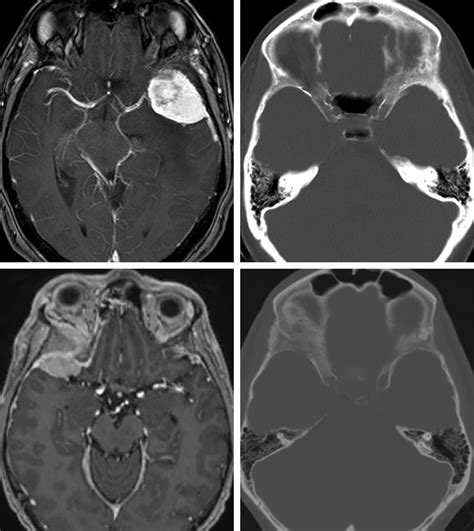

In modern medicine, diagnostic imaging is paramount for visualizing the Sphenoid Greater Wing. Plain radiographs are rarely sufficient for detailed evaluation due to the superimposition of other cranial structures. Consequently, Computed Tomography (CT) scans are the gold standard.

Magnetic Resonance Imaging (MRI) is utilized when there is a suspicion of soft tissue involvement, such as a tumor extending through the foramina into the cavernous sinus or the infratemporal fossa.

• Nerve Compression: Growths, tumors, or inflammation in the middle cranial fossa can put pressure on the nerves passing through the foramina, leading to sensory deficits in the face or motor issues, such as difficulties with chewing.

• Surgical Access: The sphenoid bone is a common landmark in neurosurgery. Approaches to the pituitary gland or the cavernous sinus often involve navigating around the greater wings.